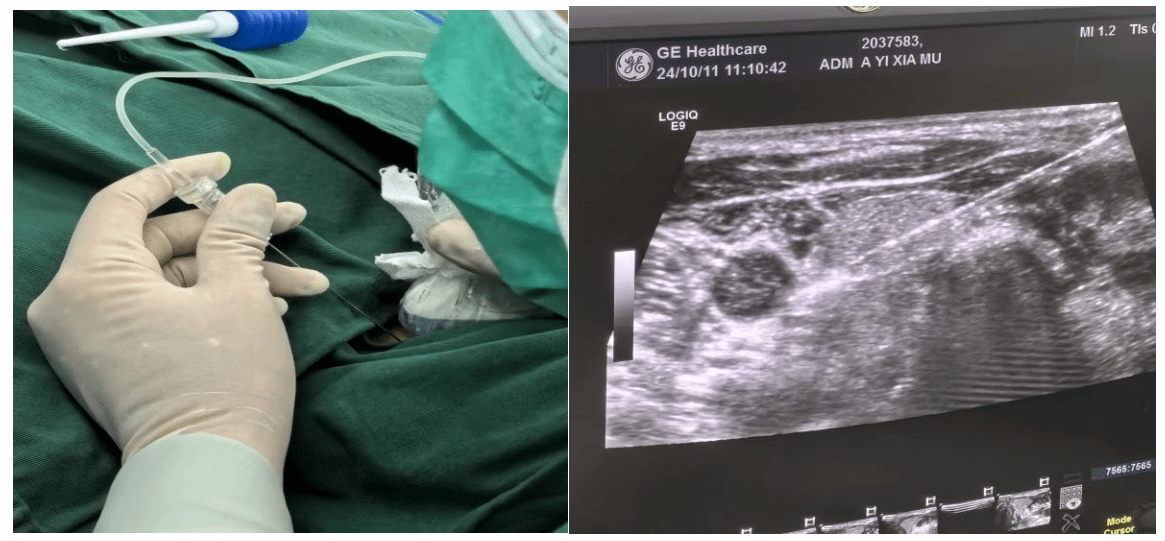

专家术中指导我院操作团队

目前超声引导下的甲状旁腺病变消融术仅需一根细针便可达到外科手术效果,缓解患者病痛,具有精准、微创、效率高及安全性相对较高等特点,术后患者即刻可以下床活动,骨痛、皮肤瘙痒症状明显缓解。这种新型治疗方式,可以让更多的终末期肾衰竭患者获益。

术中细针操作及B超引导视野